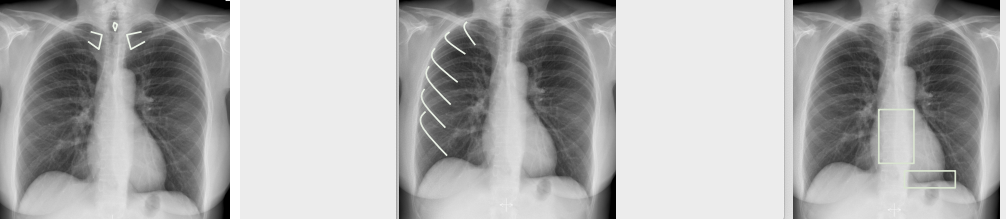

what can go wrong?

v) Everythng else

- Bones

- Soft tissue

- Other objects

whats this?

cardiopacemaker